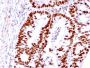

HCT116, MCF-7, A431 or HeLa cells. Colon Carcinoma.

Antibody target cellular localization

IF (verified)|IHC, FFPE (verified)|WB (verified)